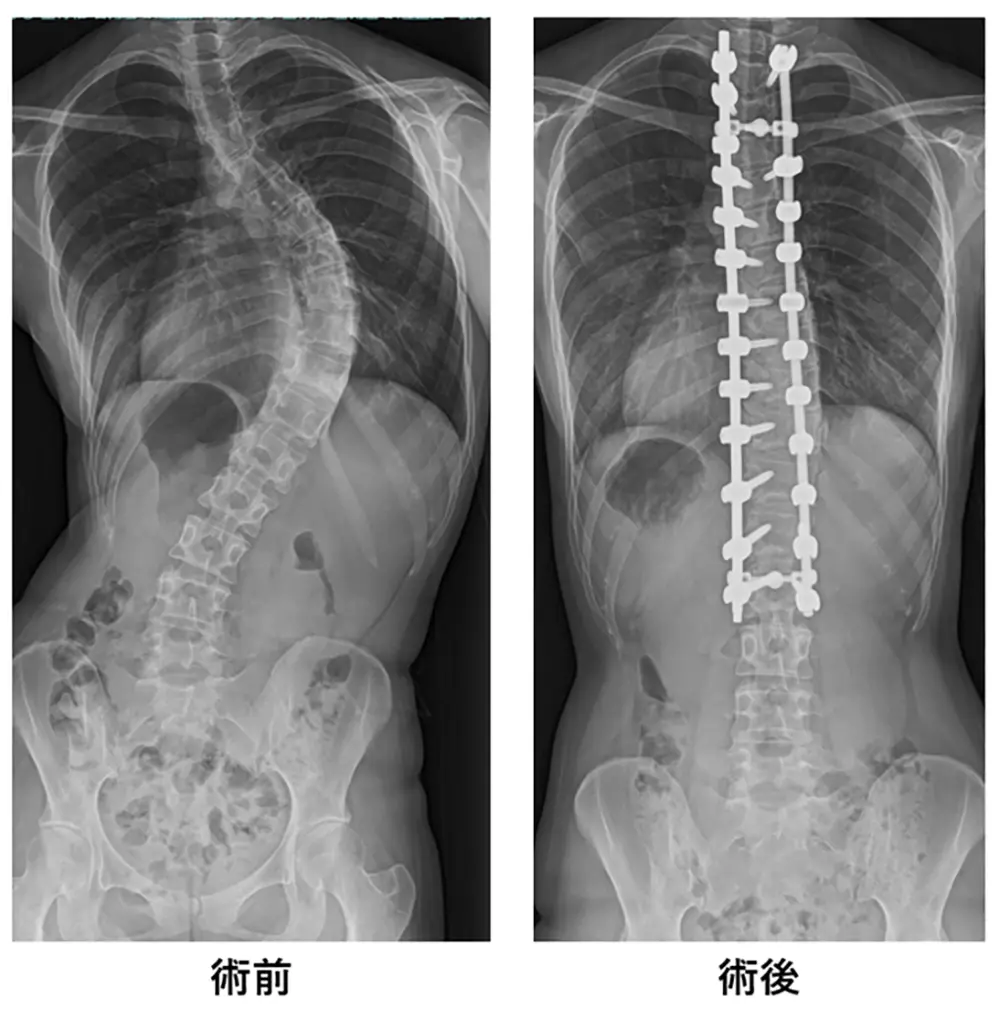

側弯症のカーブが大きい場合は手術も治療の選択肢となります。

手術療法

術前・術後